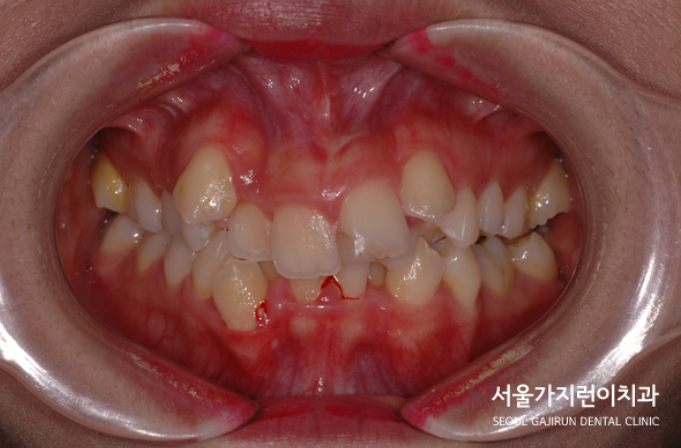

저희 치과를 찾아준 환자분의 케이스는 여러 개의 치아가 포개어져 있는 심한 덧니 케이스에 해당됐는데요. 구강위생관리가 어려웠기 때문에 덧니 때문에 양치질에 어려움을 겪어왔었다고 합니다. 그래서 잇몸이 자주 붓고 피도 많이 났다고 하는데요. 덧니와 비뚤어진 치열이 콤플렉스기도 했고 웃을 때 자신감이 없어 소극적이었다고 합니다. 그래서 마스크를 쓰고 다닐때가 좋았다고 하는데요. 환자분의 경우 치아끼리 포개진 정도가 심했기 때문에 치태와 치석이 잘 생길 수밖에 없는 구조였습니다.

그래서 환자분의 경우 치아가 정상적인 위치에 자라지 못해 덧니로 발현된 게 아닌가 싶었는데요. 환자분의 나이가 20대 초반인것을 감안하면 덧니로 인한 외모 콤플렉스가 안타까운 상황이었습니다. 그래서 저희 서울가지런이 치과 교정과 의원에서는 덧니의 원인을 파악해 교정플랜을 수립했는데요. 환자분의 경우 턱뼈가 작거나 치아가 상대적으로 큰 경우 생기는 공간 부족으로 판단하고 공간의 확보를 위해 상악, 하악의 작은 어금니를 발치한 후 초기 단계부터 미니스크류를 식립해 앞니를 배열해나갔습니다. 사실 배열이야 가능했어도 앞니의 뻐드러진 느낌까지 잡기에는 쉽지 않았는데요. 돌출감도 해결해야 했기 때문에 LAMI 테크닉을 이용한 상악 구치 후방이동을 시행했습니다. 사진을 보면 레버암과 미니스크류를 확인할 수 있습니다.